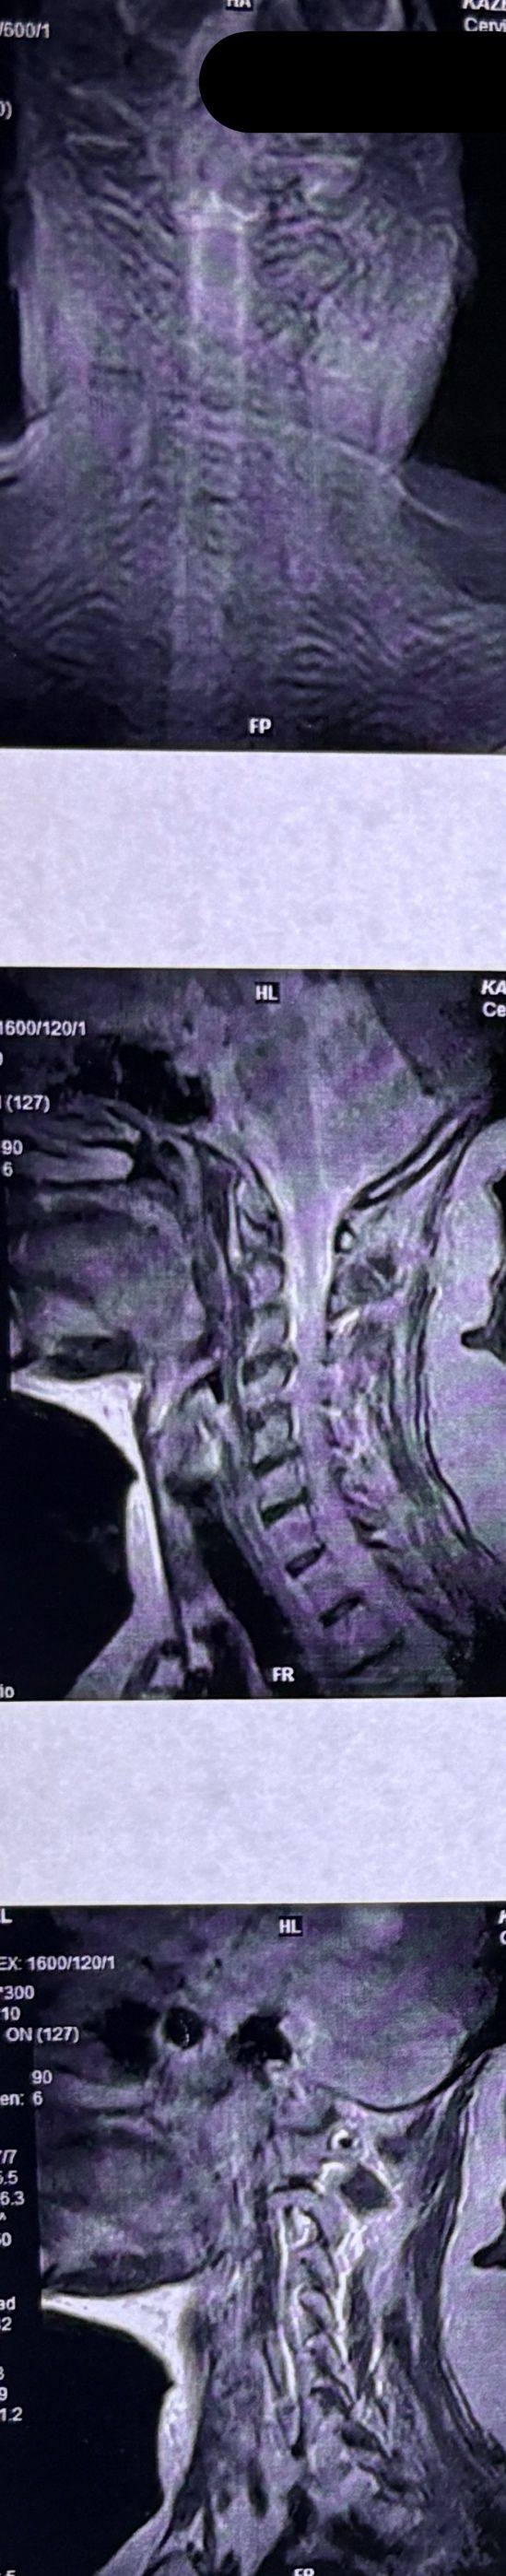

53 yrs old femal presented to my clinic on Jan/2025 with neck pain which was started 40 days ago. In the last 5 days pain was increased without any radicular pain. Had done mri and saw an experienced chiropractor and got 5 sessions of cervical adjustment/SMT which was so helpful in decreasing her pain. I repeated her cervical mri and did EMG/NCV( just had mild c5,c6 radiculopathy). In examination had no UMN signs. I have posted her mri before and after adjustments by another chiropractor.

I didn’t accept her for treatment.

Was cervical SMT a wise decision to treat her cerical disc Extrusion? What could be her complications after adjustment(even though her pain was reduced a lot after those adjustments?)

If you had visited this patient first, what would be your plan of management for her?